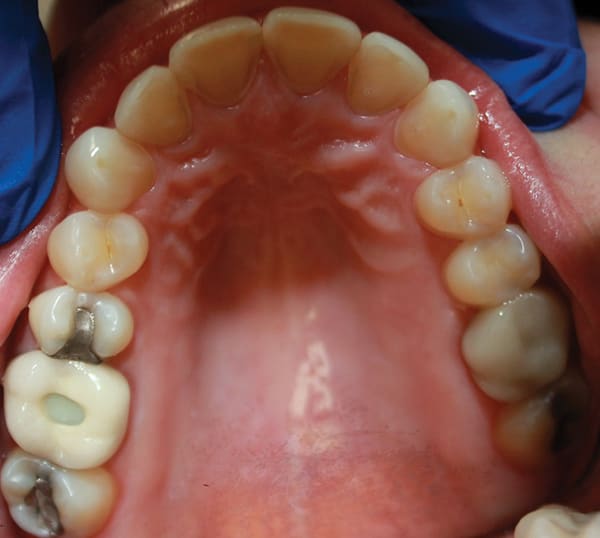

A female patient aged 57 years presented with altered passive eruption of the maxillary anterior teeth, which was diagnosed as a secondary condition to tooth erosion resulting from long-standing gastroesophageal reflux disease (GERD). Clear aligner therapy was initiated to level and align the occlusion and intrude the maxillary anterior teeth back to their original gingival position. After 18 months of poor patient compliance, improvement in tooth position was minimal and the amount of clinical overjet that was desired was not achieved. This limited the restorative armamentarium, and a decision was made to proceed with monolithic zirconia-oxide restorations. Following teeth preparation and tissue retraction, the case was impressed using an intraoral scanner (iTero® Element 2, Align Technology, Inc., itero.com). The final restorations were made of zirconium dioxide with a feldspar veneering ceramic shade 1M1 as the pressed layer on porcelain on the facials. The outcome of the case met the patient's primary concerns, achieving the lengthening and lightening of the anterior teeth that she desired. Because of the patient's continued challenges with GERD, however, she reported having difficulty with compliance related to the clear aligner therapy and whitening protocols, precluding a more ideal result. Nonetheless, the patient was pleased with her new smile and the clinician, given the challenging circumstances, was satisfied with the clinical results of the final restorations.